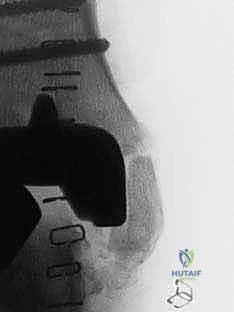

الخطوة الثالثة: إزالة المفصل القديم (Explant Removal)

يتم استخراج المكونات المعدنية والبلاستيكية لمفصل (Agility) القديم بحرص بالغ للحفاظ على ما تبقى من العظم السليم.